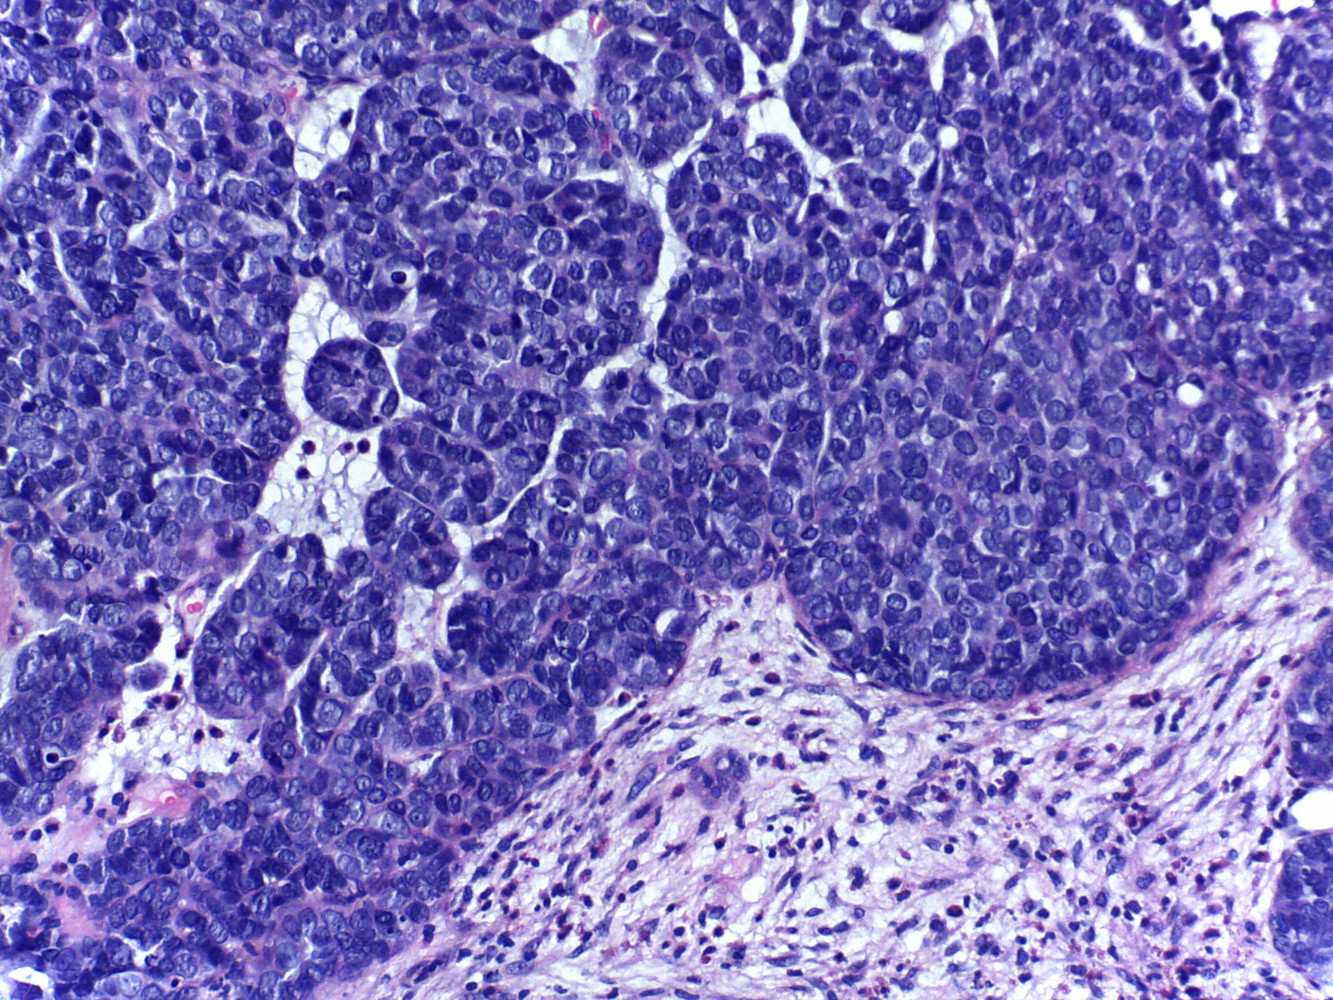

Diagnóstico: Carcinoma multifenotipico sinonasal asociado a VPH

Comentario: Anteriormente conocido como carcinoma con características semejantes al carcinoma adenoideo quístico asociado a VPH, este carcinoma se ha descrito hasta ahora solamente en tracto sinonasal, tiene características histológicas semejantes al carcinoma adenoideo quístico con componente cribiforme y tubular y un componente de carcinoma epidermoide in situ en el epitelio superficial . Todos los casos descritos están asociados a infección por VPH .